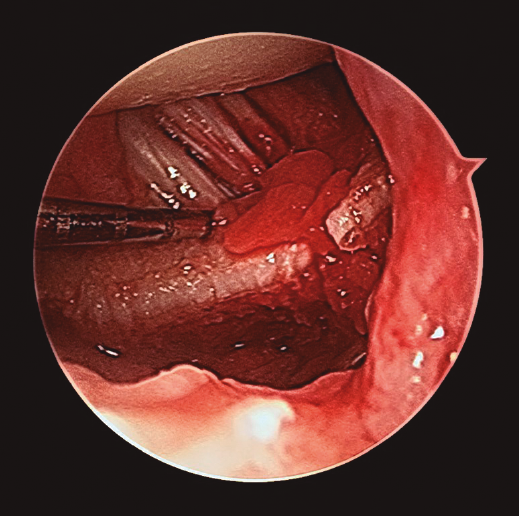

- Artroscopia de muñeca con sistema de tracción longitudinal a 10 N y vías artroscópicas estándar 3-4 y 6R para evaluar la articulación radiocarpiana y las vías mediocarpiana ulnar (MCU) y radial (MCR) en el caso de la articulación mediocarpiana, utilizando para ello una óptica de 2,3 mm y 30°(2,17), mediante técnica de artroscopia en seco(23)(Figura 2). En este tiempo quirúrgico artroscópico se evaluó: la presencia de escalón articular, la rotación de los fragmentos articulares y la existencia de lesiones asociadas al nivel del complejo del fibrocartílago articular (CFCT), así como al nivel de los ligamentos extrínsecos e intrínsecos de la muñeca(17)(Figura 3). En primer lugar, se evalúo la articulación radiocarpiana y, a continuación, la articulación mediocarpiana.

Figura 3. Desde el portal de visión radiocarpiano 3-4 observamos un importante escalón articular en la superficie de la extremidad distal del radio. Al fondo de la imagen se aprecian los ligamentos radiocarpianos volares, con integridad de los mismos.